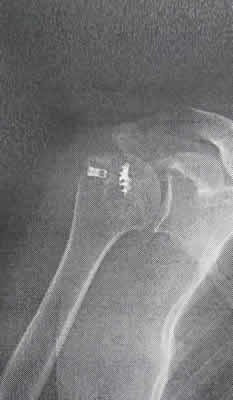

ロボット 9日目。やっと抜糸 🎵 この紋所が目に入らぬか~😁💧

レントゲンの結果もしっかりボルト🔩着いてるとの事👍 💪目指してリハビリだぁ~👊✨